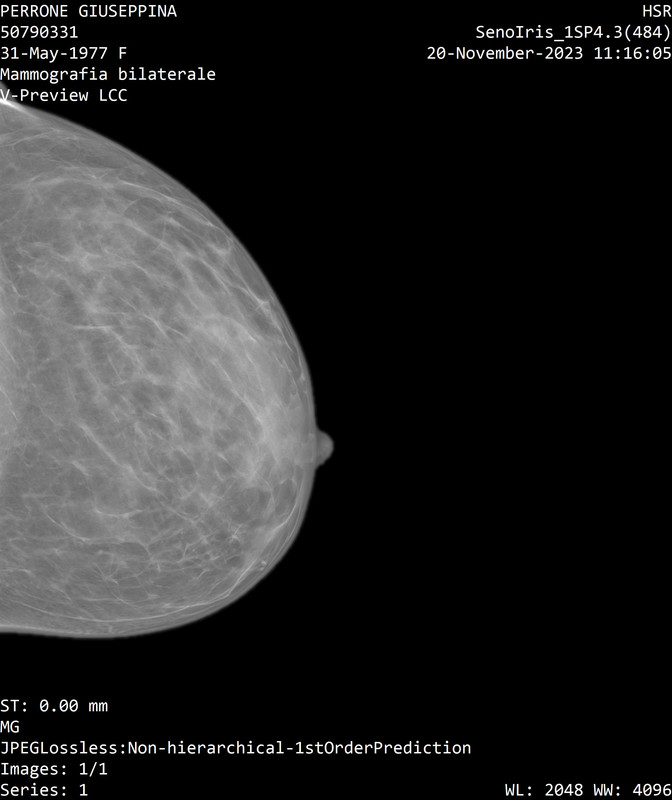

Mi scusi Dott. Catania, mi permetto ancora una volta di mandare le immagini della mammo... Penso non sia riuscito a vederle e ci tengo molto a un suo parere, visto che mi hanno solo mandato ad analizzarle senza dirmi altro...

è stato

al passaggio tra i qudranti inferiori e' meglio visibile un focolaio di microcalcificazioni non riconoscibile con certezza all'eco mirata, meritevole di caratterizzazione mediante agobiopsia con sistema VAB sotto guida mammografica.

Mi scusi l'insistenza